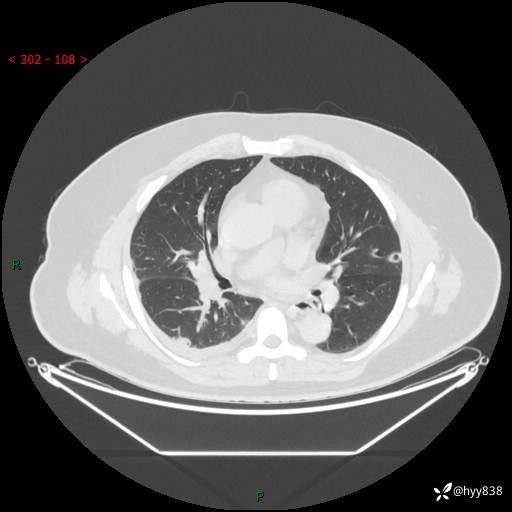

病例信息

性别:男

年龄:48岁

简要病史:发热来诊(门诊病人)

胸部CT平扫